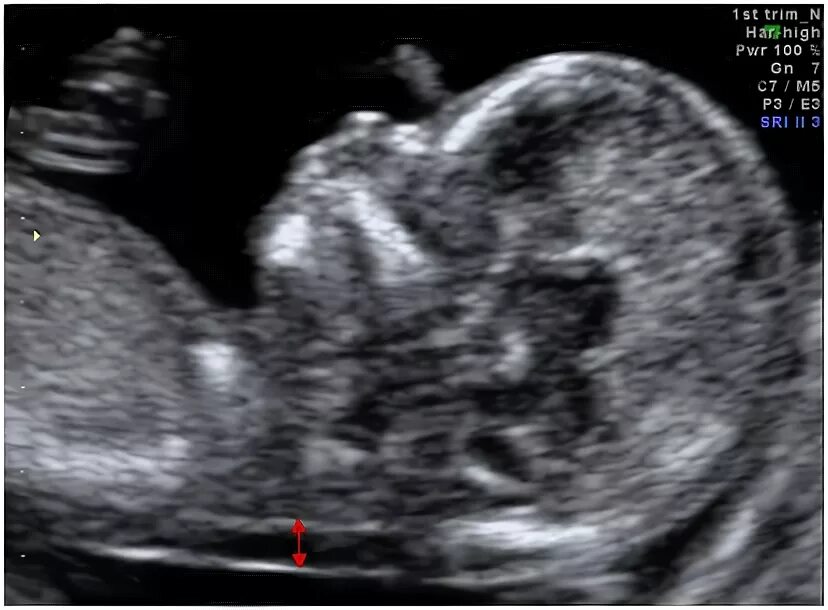

Узи аномалий